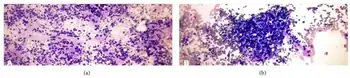

a)Lymphocytic (Hashimoto) thyroiditis-polymorphous lymphoid population b) Lymphocytic (Hashimoto) thyroiditis-lymphohistiocytic aggregates

a)Lymphocytic (Hashimoto) thyroiditis-polymorphous lymphoid population b) Lymphocytic (Hashimoto) thyroiditis-lymphohistiocytic aggregates Ultrasound imaging of the thyroid gland (right lobe longitudinal) in a person with Hashimoto thyroiditis.